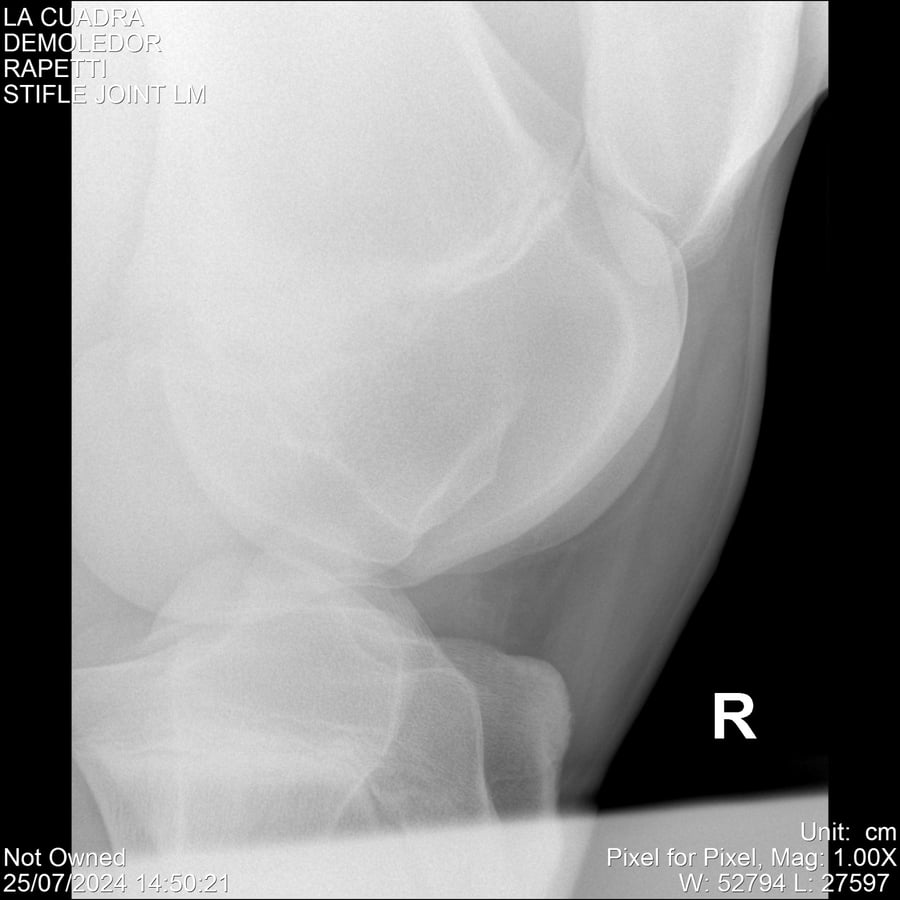

LOTE 14, DEMOLEDOR 🔥 🔥 🔥 Lote Anterior Volver al remate Lote Siguiente Ficha Contacto Montevideo - Ficha del Lote Identificador: #284454 Categoría: Yeguarizos Montevideo - 89 Visualizaciones ClicData Contacto Empresa: Abelenda N. R., Walter Hugo Nombre*: Teléfono* : E-mail* : Mensaje Enviar Registrese gratis Este contenido Exclusivo está disponible sólo para usuarios registrados Ingresar